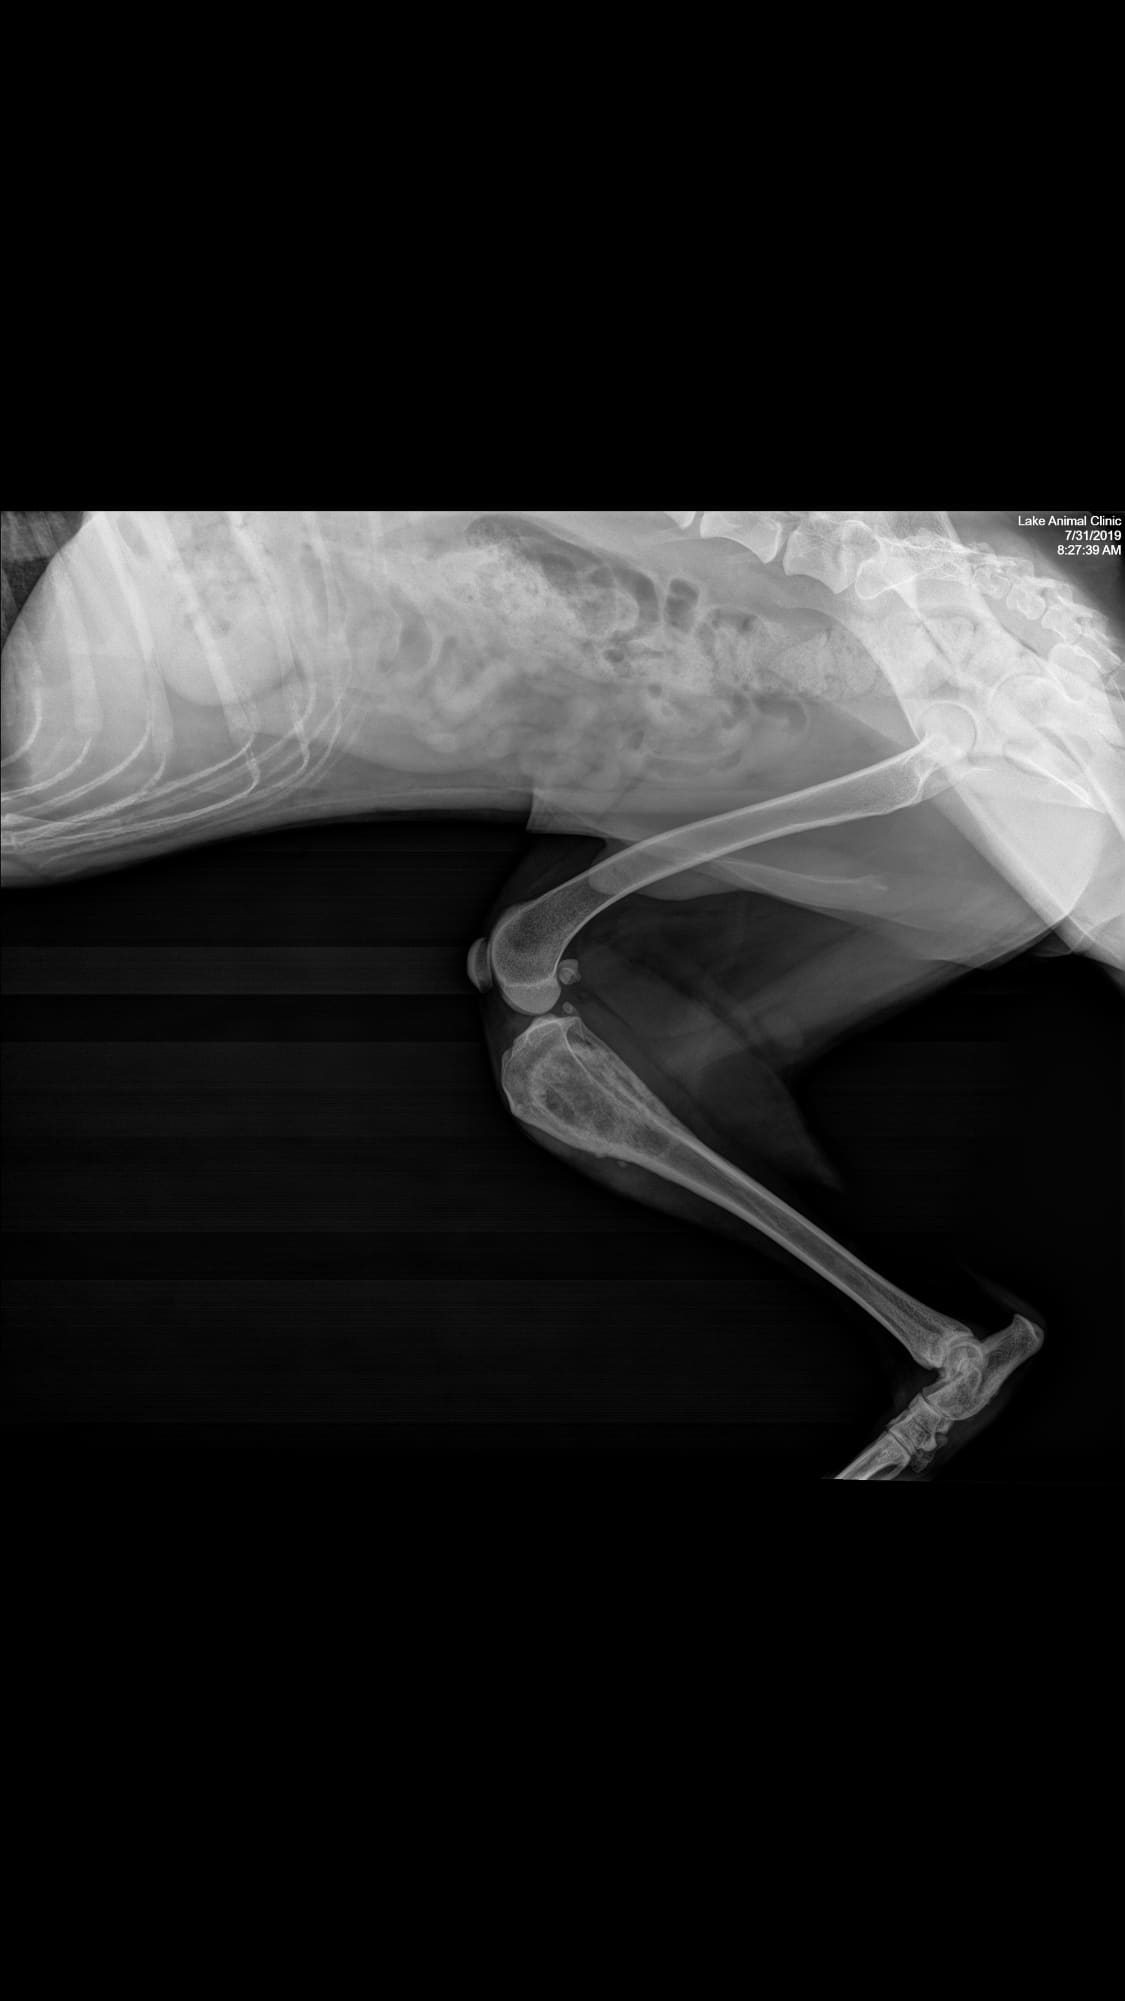

Pet's info: Dog | Goldendoodle | Male | 4 years and 4 months old | 48 lbs

Is this osteosarcoma? My vet said it was but could it be anything else?

Thanks for using Petco Pet Education Center, formerly Petcoach! I would agree that the primary differential based on this radiographs would be a primary bone tumor being osteosarcoma the most common one. However, other things such as a fungal infection depending on the state you live in, is also possible. The next step would be sampling of this lesion via fine needle aspiration or biopsy to confirm the diagnosis. If confirmed, therapy can be discussed at that time. I'm hoping for the best!